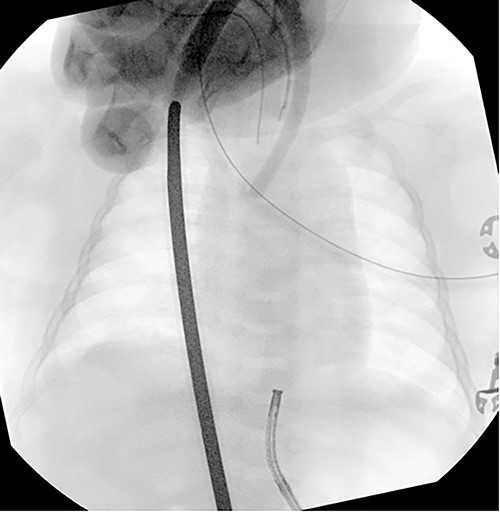

On day of life 15, an esophageal gap study was performed, which demonstrated a proximal esophageal pouch ending at the T2 vertebral level and a 7-mm distal esophageal stump, with an estimated esophageal gap of 6 cm (Fig. 3). The infant remained in the neonatal intensive care unit (NICU) awaiting long-gap esophageal atresia repair until 4 months of age when repeat esophageal gap study demonstrated a gap of approximately six vertebral bodies. He then underwent gastric pull-up, pyloroplasty and jejunostomy tube placement. Post-operative esophagram demonstrated no leak, and the infant was discharged home 3 weeks post-operatively with close follow-up.

Esophageal gap study performed on day of life 15 demonstrating an estimated esophageal gap of ~6 cm.